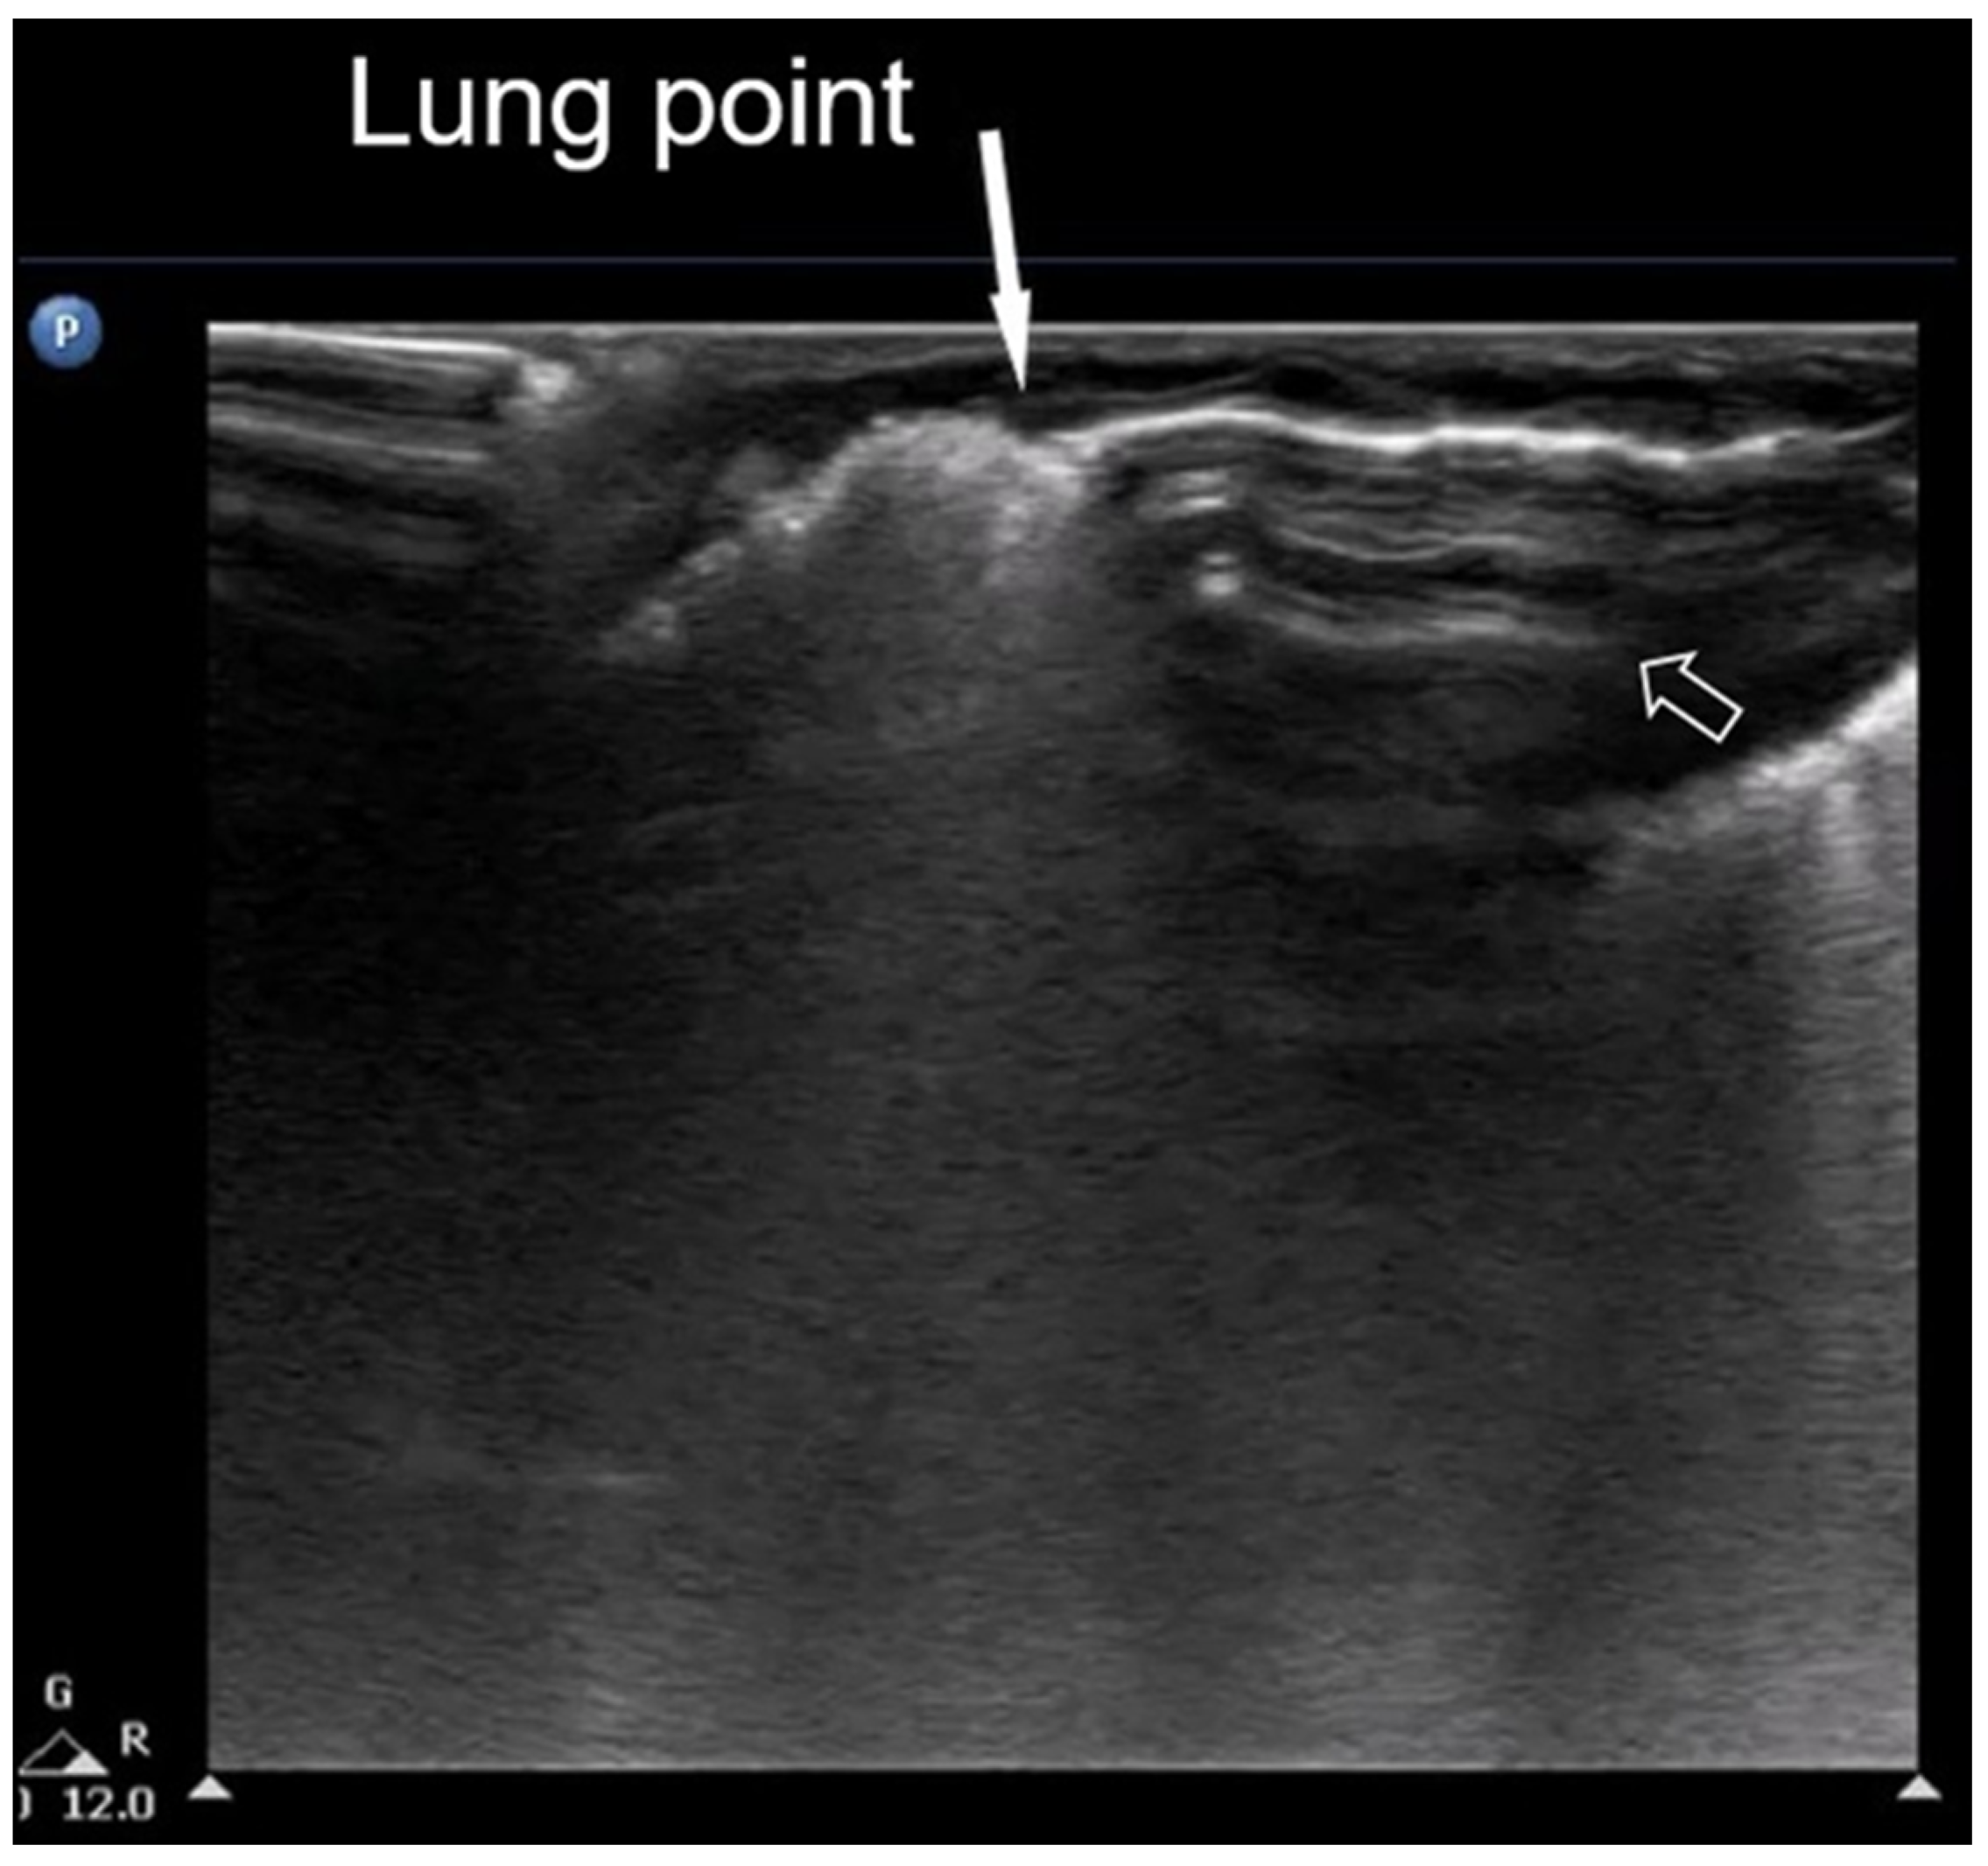

3.1.7. Lung Point Sign

The “lung point” or “lung point sign” is a highly specific lung sonographic sign which helps in the diagnosis of pneumothorax and can also facilitate the assessment of pneumothorax severity. In particular, the severity of pneumothorax depends on its position relative to the anatomical lines that define the regions of the chest. In LUS, the “lung point” is defined as the boundary between the area without normal lung sliding (i.e., pneumothorax) and the area where normal lung sliding is present (normal lung) (Figure 8) [4,12,15,16,25,26].

Figure 8.

Lung point sign: The transition point between the aerated lung with coalescent B-lines (which probably represents respiratory distress syndrome) which are absent in pneumothorax and the area with A-lines (transparent arrow) but without lung sliding (absent in pneumothorax in real-time scanning).